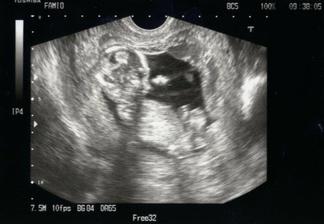

12.2.2010, 20+0tt - II.UTZ - AS+ pravid., BPD- 47(19+4), FL- 29(19+3), HC- 167(19+2), AC- 146(19+5), srdce- 4loc xvc, plod.voda norm., placenta ventric. nedosah do DDS, sonoanatom. norm. masc., odhadovaná váha- 300g.